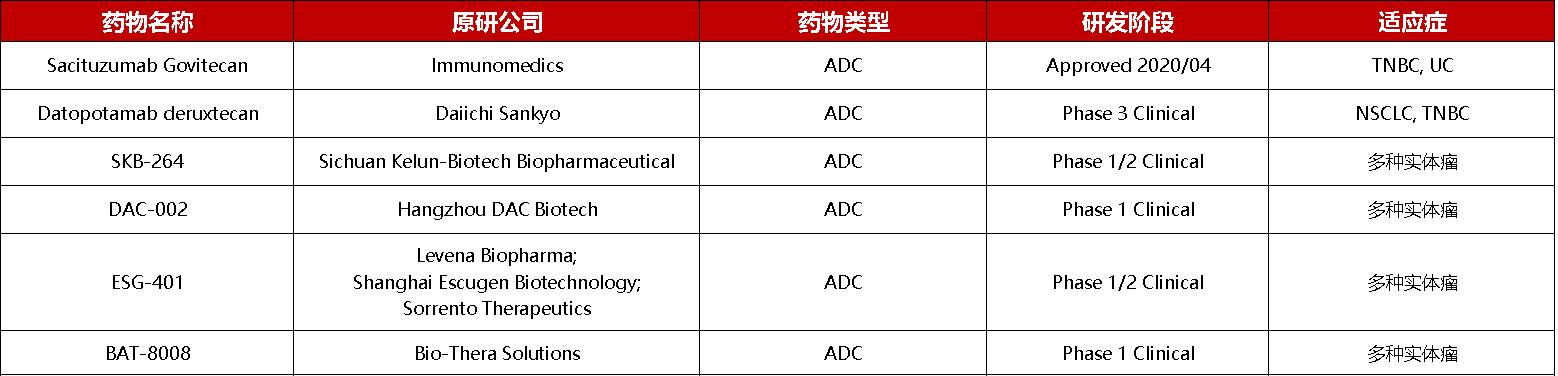

TROP2靶向药物开发情况

如表所示,TROP2靶向药物的开发主要集中在单抗、ADC方向,药物适应症为三阴性乳腺癌、尿路上皮癌、非小细胞癌及其他多种实体瘤。在临床前TROP2靶药研究中,除了靶向TROP2的单抗ADC药物外,靶向CD3-TROP2双抗、CAR-T以及CAR-NK等方向的药物研究也在进行中。

TROP2药物开发信息